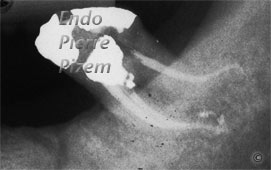

L’OPMI PROergo VS la calcification extrême d’un système canalaire d’une dent pilier

Avantages du microscope opératoire en endodontie. Étude de cas numéro: 448115 Cas référé pour un traitement endodontique sur une seconde